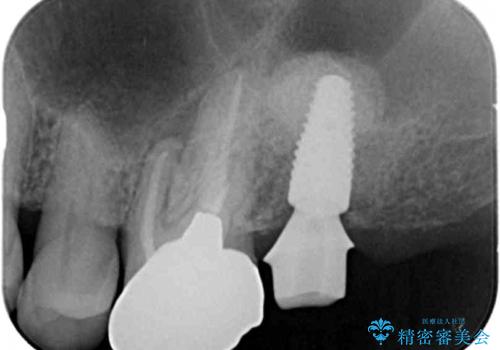

上顎洞が近接しており上顎骨の厚みが薄いことから、ソケットリフト(上顎洞底挙上術)をインプラント埋入と同時に行いました。

奥歯でしっかりと咬むことができるようになり、ご満足頂けました。

初診時から治療終了時までのレントゲンをお見せして説明差し上げたところ、「お~!骨ができている!」と喜んで下さいました。

ソケットリフトにより上顎洞底を挙上し骨造成することにより、骨の厚みが薄い部分でもインプラントが可能になります。

インプラントの種類:ストローマン BLT

クラウンの種類:メタルボンドクラウン エコノミー